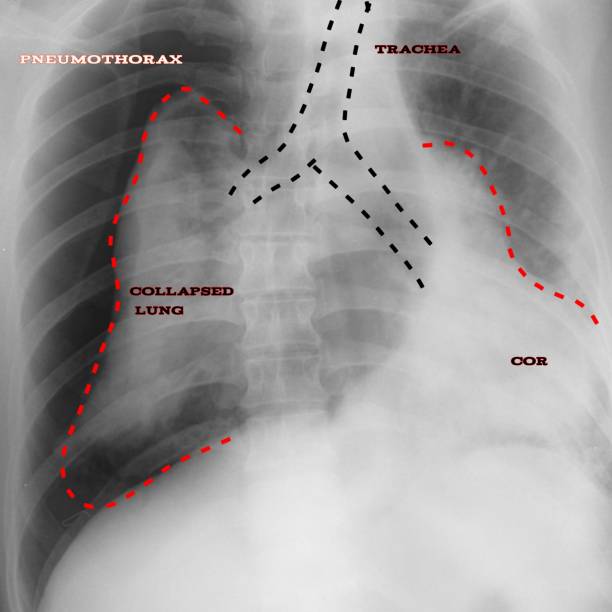

기흉(pneumothorax)은 폐와 흉부벽 사이에 공기가 쌓이는 상태를 말합니다. 이는 폐가 공기로 가득 차면서 폐가 축소되고 압축되어 발생합니다. 이러한 압축으로 인해 폐의 기능이 저하되며 호흡 곤란, 가슴 통증 등의 증상을 유발할 수 있습니다.

흉부 X선 검사

기흉이 의심되는 환자에게는 흉부 X선 검사를 실시하여 기흉이 있는지 확인할 수 있습니다. 이 방법은 비교적 쉽고 빠르게 기흉을 진단할 수 있습니다.